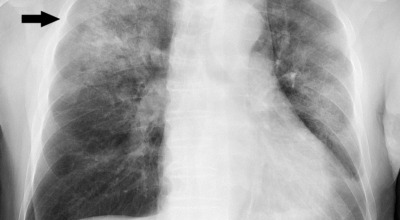

1. 금연

장기간 흡연은 기도의 보호 메커니즘을 손상시켜 기관, 기관지, 폐포 또는 폐 조직에 해를 끼쳐 폐 기능 저하에 영향을 줄 수 있습니다.